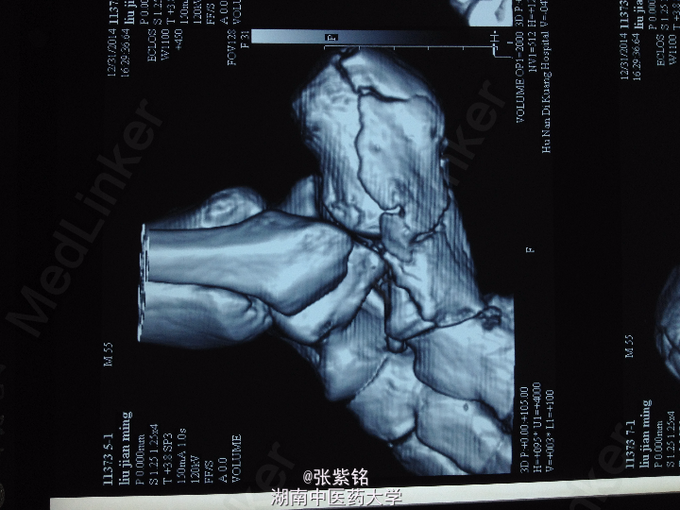

查体:左足部肿胀明显,可见大面积皮下青紫瘀斑,压痛明显,尤以足跟部为甚,左足跟部可扪及明显骨擦音,足踝关节主动活动受限,被动活动疼痛明显加重,左足背动脉搏动可扪及,伤肢血运感觉可。 辅查:左足正斜位片示:左跟骨骨折。 左足CT平扫+三维重建:左跟骨骨质连续性中断,可见多发骨折线,骨折端对位对线不良,并可见多块碎骨片,骨折线累积关节面,左足软组织明显肿胀;左跟骨粉碎性骨折。

诊断:左跟骨粉碎性骨折 处理:石膏外固定,切开复位钢板螺钉内固定术。 术后14日左足跟部切口处中段皮肤软组织坏死,切口未愈合,钢板螺钉外露,切口处感染。 细菌培养+药敏结果:凝固酶阴性葡萄球菌。 予以VSD切口处负压引流7日后拆除,行取皮植皮术,术后皮片坏死。